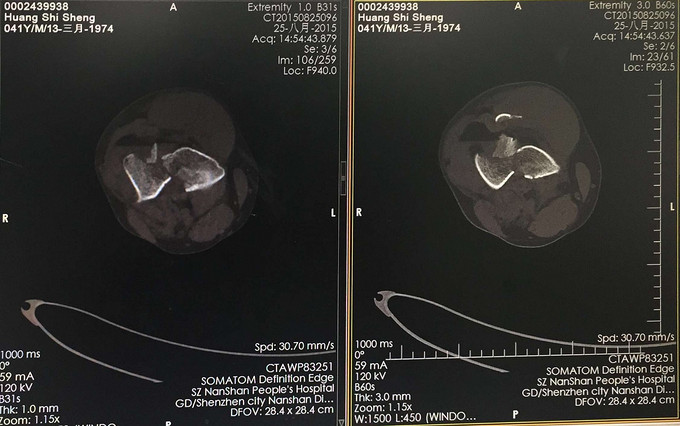

查体:右大腿中下段短缩成角畸形,肿胀,可扪及骨擦感,患肢末梢感觉血运可。 X:右股骨下端骨折 CT:右股骨下端骨折,波及关节面。

右股骨远端粉碎性骨折 完善检查,行右股骨远端骨折切开复位内固定术。